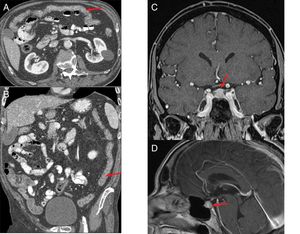

Figure 8.(A and B) Patient with stage IV squamous cell carcinoma of the lung, on third-line treatment with nivolumab, presenting with diarrhoea and a febrile episode. Computed tomography (CT) shows a slight diffuse wall thickening with increased enhancement of the mucosa of the colon (arrows), which extends from the transverse colon to the rectum, suggestive of colitis. (C and D) Patient with stage IV renal carcinoma due to pulmonary involvement, being treated in a clinical trial with combined nivolumab and ipilimumab therapy. The patient had a history of very intense headache for several days, without pyrexia and with normal brain CT. The magnetic resonance imaging (MRI) volumetric interpolated breath-hold examination (VIBE) (C) and T1 sequences with contrast (D) show the pituitary gland to be enlarged in relation to the age of the patient (craniocaudal diameter 9mm), with a convex-shaped superior margin and homogeneous enhancement which, in the clinical context of the patient is suggestive of immune checkpoint inhibitor-induced hypophysitis.

Hypophysitis: hypophysitis has primarily been associated with treatment with ipilimumab. It tends to occur nine weeks after starting treatment and has an incidence of 2–4%.31 Initial symptoms are headache and fatigue, followed by hypothyroidism, hypogonadism and hypocortisolism.30

Araujo et al.37 reviewed the cases of 57 patients with ipilimumab-related hypophysitis and identified abnormal imaging findings in 77%. Typical imaging findings are a symmetrical increase in the size of the pituitary gland, which acquires a convex shape, with thickening of the stalk or infundibulum, and homogeneous enhancement after the administration of contrast (Fig. 8C and D). After corticosteroid treatment, follow-up images may show a decrease in pituitary size, a change in shape from convex to concave, and even in extreme cases an empty sella turcica. The majority of patients have no recovery of pituitary function.37,38